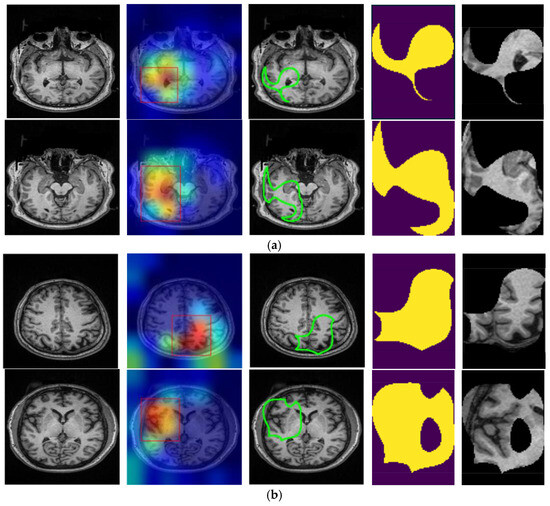

In this study, Grad-CAM was employed to identify the important regions in MR images that contributed most significantly to the classification of bipolar disorder and schizophrenia. Figure 3a,b illustrates sample images from individuals diagnosed with SCH, bipolar disorder, and their corresponding Grad-CAM heatmap results. As shown in Figure 4, the Grad-CAM heatmaps highlight the areas within each image that the model focused on during classification. After the heatmap is created, in order to identify the regions of interest highlighted by Grad-CAM, we apply a threshold value to the generated heatmap. If both red and green channel intensities exceed a value of 125, these areas are selected as important regions. This threshold value was determined through trial and error. In cases where two independent regions are identified, the region with the higher average intensity within its bounding box is prioritized as the primary area of interest. After that, we extract region-based features from the important areas determined by Grad-CAM. These features are area, centroid, eccentricity, orientation, extent, perimeter, solidity, major axis length, minor axis length, convex area, Euler number, and equivalent diameter. In addition to region-based features, statistical features such as minimum, maximum, variance, and entropy are also extracted from the important regions.

Figure 3. Sample Grad-CAM results of (a) SCH and (b) bipolar disorder.

Applsci 15 01717 g003

Figure 4. Original T1-weighted MR image, Grad-CAM heatmaps, the focused areas created from the heatmaps as contoured regions, corresponding binary masks, and masked areas on the T1 images of (a) SCH and (b) bipolar disorder.

Applsci 15 01717 g004